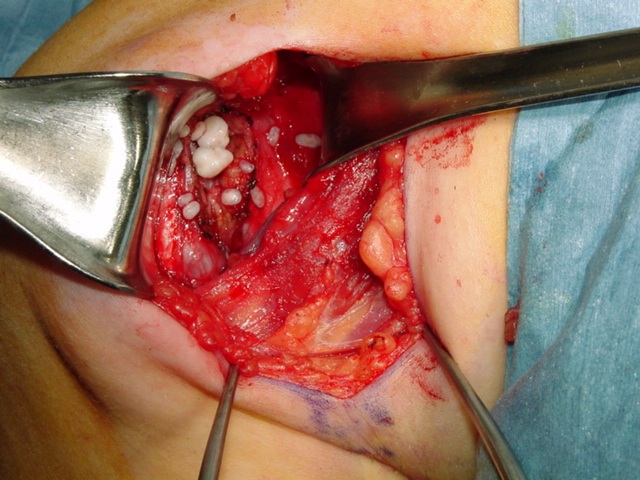

The treatment for synovial chondromatosis is the excision of the involved synovium and removal of the cartilage nodules (Fig. 6, Fig. 10-11). Recurrence is infrequent although it may recur in cases where removal is incomplete or synovium is affected diffusely. Malignant transformation is seen in less than 5% of the cases and is usually a low grade malignancy (synovial chondrosarcoma). Some papers suggest that degenerative arthritic changes still progress in the involved joint after surgical removal. In other words surgical removal may not prevent development of arthritis in the affected joint.

Fig 10 & 11. Intra-operative photographs demonstrate nodules of cartilage in the right shoulder joint (Fig. 10) and resection of the synovium (Fig. 11).